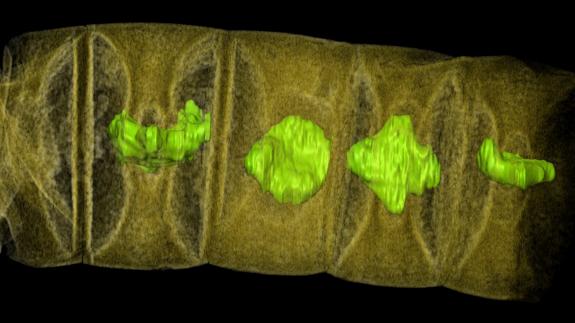

El científico británico recibió el Nobel de Fisiología o Medicina en 2002 por su contribución a la comprensión del mecanismo que permite a los genes controlar la división y la muerte celular a fin de conformar un organismo completo